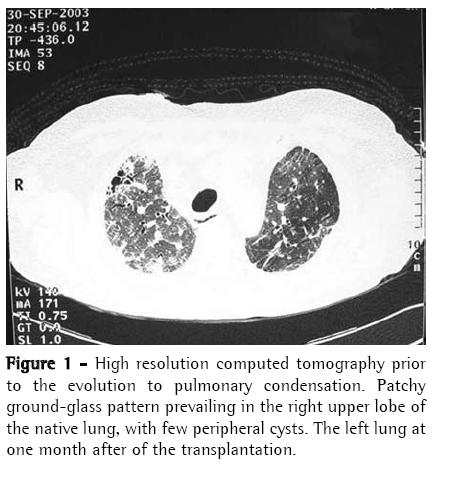

Case ReportA 56-year-old man diagnosed with IPF (using clinical, functional, tomographic and pathological criteria) five years prior, progressively evolved to dyspnea upon exertion and intense difficult-tocontrol cough with sparse mucoid expectoration. In the month preceding the lung transplantation, he presented hypoxemia and hypercapnia (arterial blood gas analysis with a PaO2 of 57 mmHg and arterial carbon dioxide tension of 45 mmHg at rest on room air at sea level), diffusing capacity of the lung for carbon monoxide at 29% of the predicted value, forced vital capacity of 40.8% (1.41 L), and forced expiratory volume in one second of 52.6% (1.31 L). Pulmonary perfusion scintigraphy revealed arterial flow of 76.7% for the right lung and 23.3% for the left lung. The laboratory tests for collagen-related diseases and the epidemiological investigation of known interstitial diseases were negative. During the five years of outpatient monitoring, the patient had been treated with corticosteroids (prednisone, 0.25 to 1 mg/kg/day), immunosuppressive agents (azathioprine or cyclophosphamide, 0.5 to 2 mg/kg/day), and an antifibrotic/immunomodulatory agent (interferon-γ1b) for four months. The transplantation was unilateral at left, corresponding to the minimal arterial perfusion and the greater intensity of the interstitial involvement according to the high-resolution computed tomography (HRCT) scan. Immediately after surgery, the patient evolved to thoracic instability due to the fracture of three ribs as a result of the osteopenic rib traction during the closure of the incision. He also presented ischemia of severe pulmonary reperfusion (arterial blood gas analysis with a PaO2/fraction of inspired oxygen ratio = 124). The patient was tracheostomized and remained on invasive mechanic ventilation (MV) for ten days, progressively recovering from hypoxemia. The immunosuppressive regimen began with 5 mg/kg of cyclosporine (12/12 h), 0.5 mg/kg/day of prednisone, and 2 mg/kg/day of azathioprine. In addition, anti-basiliximab interleukin-2 antibody was administered on postoperative days 1 and 4. Anti-methylprednisolone antibody (1 g) was also administered postoperatively. The patient was discharged from the intensive care unit to the semi-intensive care unit. However, on the eighth day in the semi-intensive care unit, he presented exacerbation of dyspnea, accompanied by the return of the dry cough and progressive crackling rales throughout the right hemithorax, and was therefore re-admitted to the intensive care unit. The patient was again submitted to an HRCT scan. In addition, fiberoptic bronchoscopy with bronchoalveolar lavage (BAL) was performed, together with transbronchial biopsy of the left lower lobe and the right upper lobe. All cultures tested negative, the BAL fluid presented a neutrophilic pattern, without eosinophils or hemosiderin-laden macrophages, and the histopathological analysis was inconclusive. A pulmonary arteriogram was performed, followed by thoracoscopic lung biopsy in three different regions of the right upper lobe to ensure that the disease was representative (Figures 1 and 2). The pulmonary arteriogram did not demonstrate thromboembolic disease. The biopsy culture was negative for bacteria, fungi, and mycobacteria. Herpes simplex virus and cytomegalovirus tests were also negative. Direct immunofluorescence for Chlamydia pneumoniae, Legionella pneumophila, and Mycoplasma pneumoniae, as well as for antigenuria for L. pneumophila serotype 1, were negative. The histological study of the biopsy of the three right lung areas showed an exclusive pattern of UIP, similar to the left native lung (Figure 3). Pulse therapy with 1 g of methylprednisolone was performed for three consecutive days. The patient remained on invasive MV, then evolved to sepsis caused by infection with Klebsiella pneumophila and Pseudomonas aeruginosa. On day 141 of the hospital stay, after the patient had been on invasive MV and using noradrenaline (0.2 µg/kg/day) for 109 days, transplant of the right native lung was carried out - bilateral sequential transplantation with more than a month interval - regardless of the relative contraindications: high dose of corticosteroid (>20 mg/day), MV, and sepsis treatment. (6)

The radiological imaging demonstrated condensation in the middle, upper, and lower right lobes, and the established diagnosis was IPF exacerbation in the native lung, mainly characterized by the UIP histological aspect (nonuniform and multifocal infiltrate, with inflammatory and fibrous thickening of the alveolar interstitium, pulmonary cysts, peribronchiolar fibrosis, alveolar hyperplasia, and absence of hyaline membranes), and the absence of microbial increase in lung tissues and cardiovascular decompensation. It is known that, in IPF, the lung becomes progressively collapsed, which can simulate images of pulmonary condensation. The accelerated variant of IPF has recently been described and should have its diagnosis characterized by ruling out other causes of exacerbation. The literature mentions, in unilateral lung transplantation, chronic progression of IPF in the native lung. However, there have been no reports of acute progression. This is the first case described in the national literature as IPF in its accelerated phase.